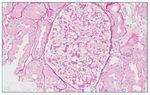

Con el diagnóstico de síndrome nefrítico, se realizó biopsia renal percutánea. La muestra incluía 34 glomérulos por sección, 25 de ellos (73%) globalmente esclerosados con restos de material hialino. De los 7 glomérulos restantes, 2 no mostraban alteraciones relevantes (fig. 2), mientras que los demás presentaban intensa proliferación endocapilar segmentaria o, más frecuentemente, global con ocasional cariorrexis y marcada hiperplasia/ hipertrofia del epitelio visceral (podocitos), con formación de seudosemilunas (figs. 3 y 4). No se identificó colapso de los capilares glomerulares ni lesiones en el polo tubular de glomérulos. Los podocitos hiperplásicos mostraban signos de reabsorción proteica y, además, se apreciaban áreas de adherencia flóculo-capsular en 2 de los glomérulos (fig. 5). También se apreciaban amplios parches de atrofia tubular, con intenso infiltrado inflamatorio acompañante y fibrosis intersticial, por lo general coincidiendo con glomérulos esclerosados, que suponen aproximadamente un 40% del área cortical. De forma ocasional se observaban túbulos dilatados con contenido proteico y/o hemático. No se identificaron depósitos hialinos en las paredes arteriolares, pero todas ellas mostraron una llamativa hipertrofia concéntrica de la capa muscular con marcada reducción y casi obliteración de la luz capilar (fig. 6). Las arterias interlobulares/ arcuatas mostraban menor grado de hiperplasia que la media sin alteraciones significativas de la íntima. No se observaron focos de necrosis fibrinoide ni trombos capilares en los glomérulos ni en las arteriolas. En el estudio de inmunofluorescencia directa se apreciaban únicamente depósitos glomerulares irregulares de IgM (1+) y C3 (2+) (fig. 7). Se realizó estudio de microscopia electrónica a partir del material incluido en parafina, y los hallazgos fueron de valoración limitada debido a la mala preservación tisular. Seis de los 7 glomérulos de la muestra se encontraban globalmente esclerosados y el restante mostraba esclerosis segmentaria; en su zona no esclerosada se observó pérdida de integridad de los endotelios y pérdida parcial de integridad de las células epiteliales viscerales, con intensa fusión de los pedicelos en las áreas mejor conservadas (fig. 8). La falta de integridad de las paredes capilares no permitía una medición correcta de su grosor, aunque, en las láminas densas conservadas se apreciaban algunas irregularidades y algunas laminaciones, así como zonas de menor grosor y zonas de mayor severidad en el espesor de la membrana de la lámina densa. No se observaron depósitos electrón-densos. Con estos hallazgos se diagnosticó de glomeruloesclerosis focal y segmentaria, variante celular.

Figura 2. Glomérulo sin alteraciones relevantes. PAS ×20.